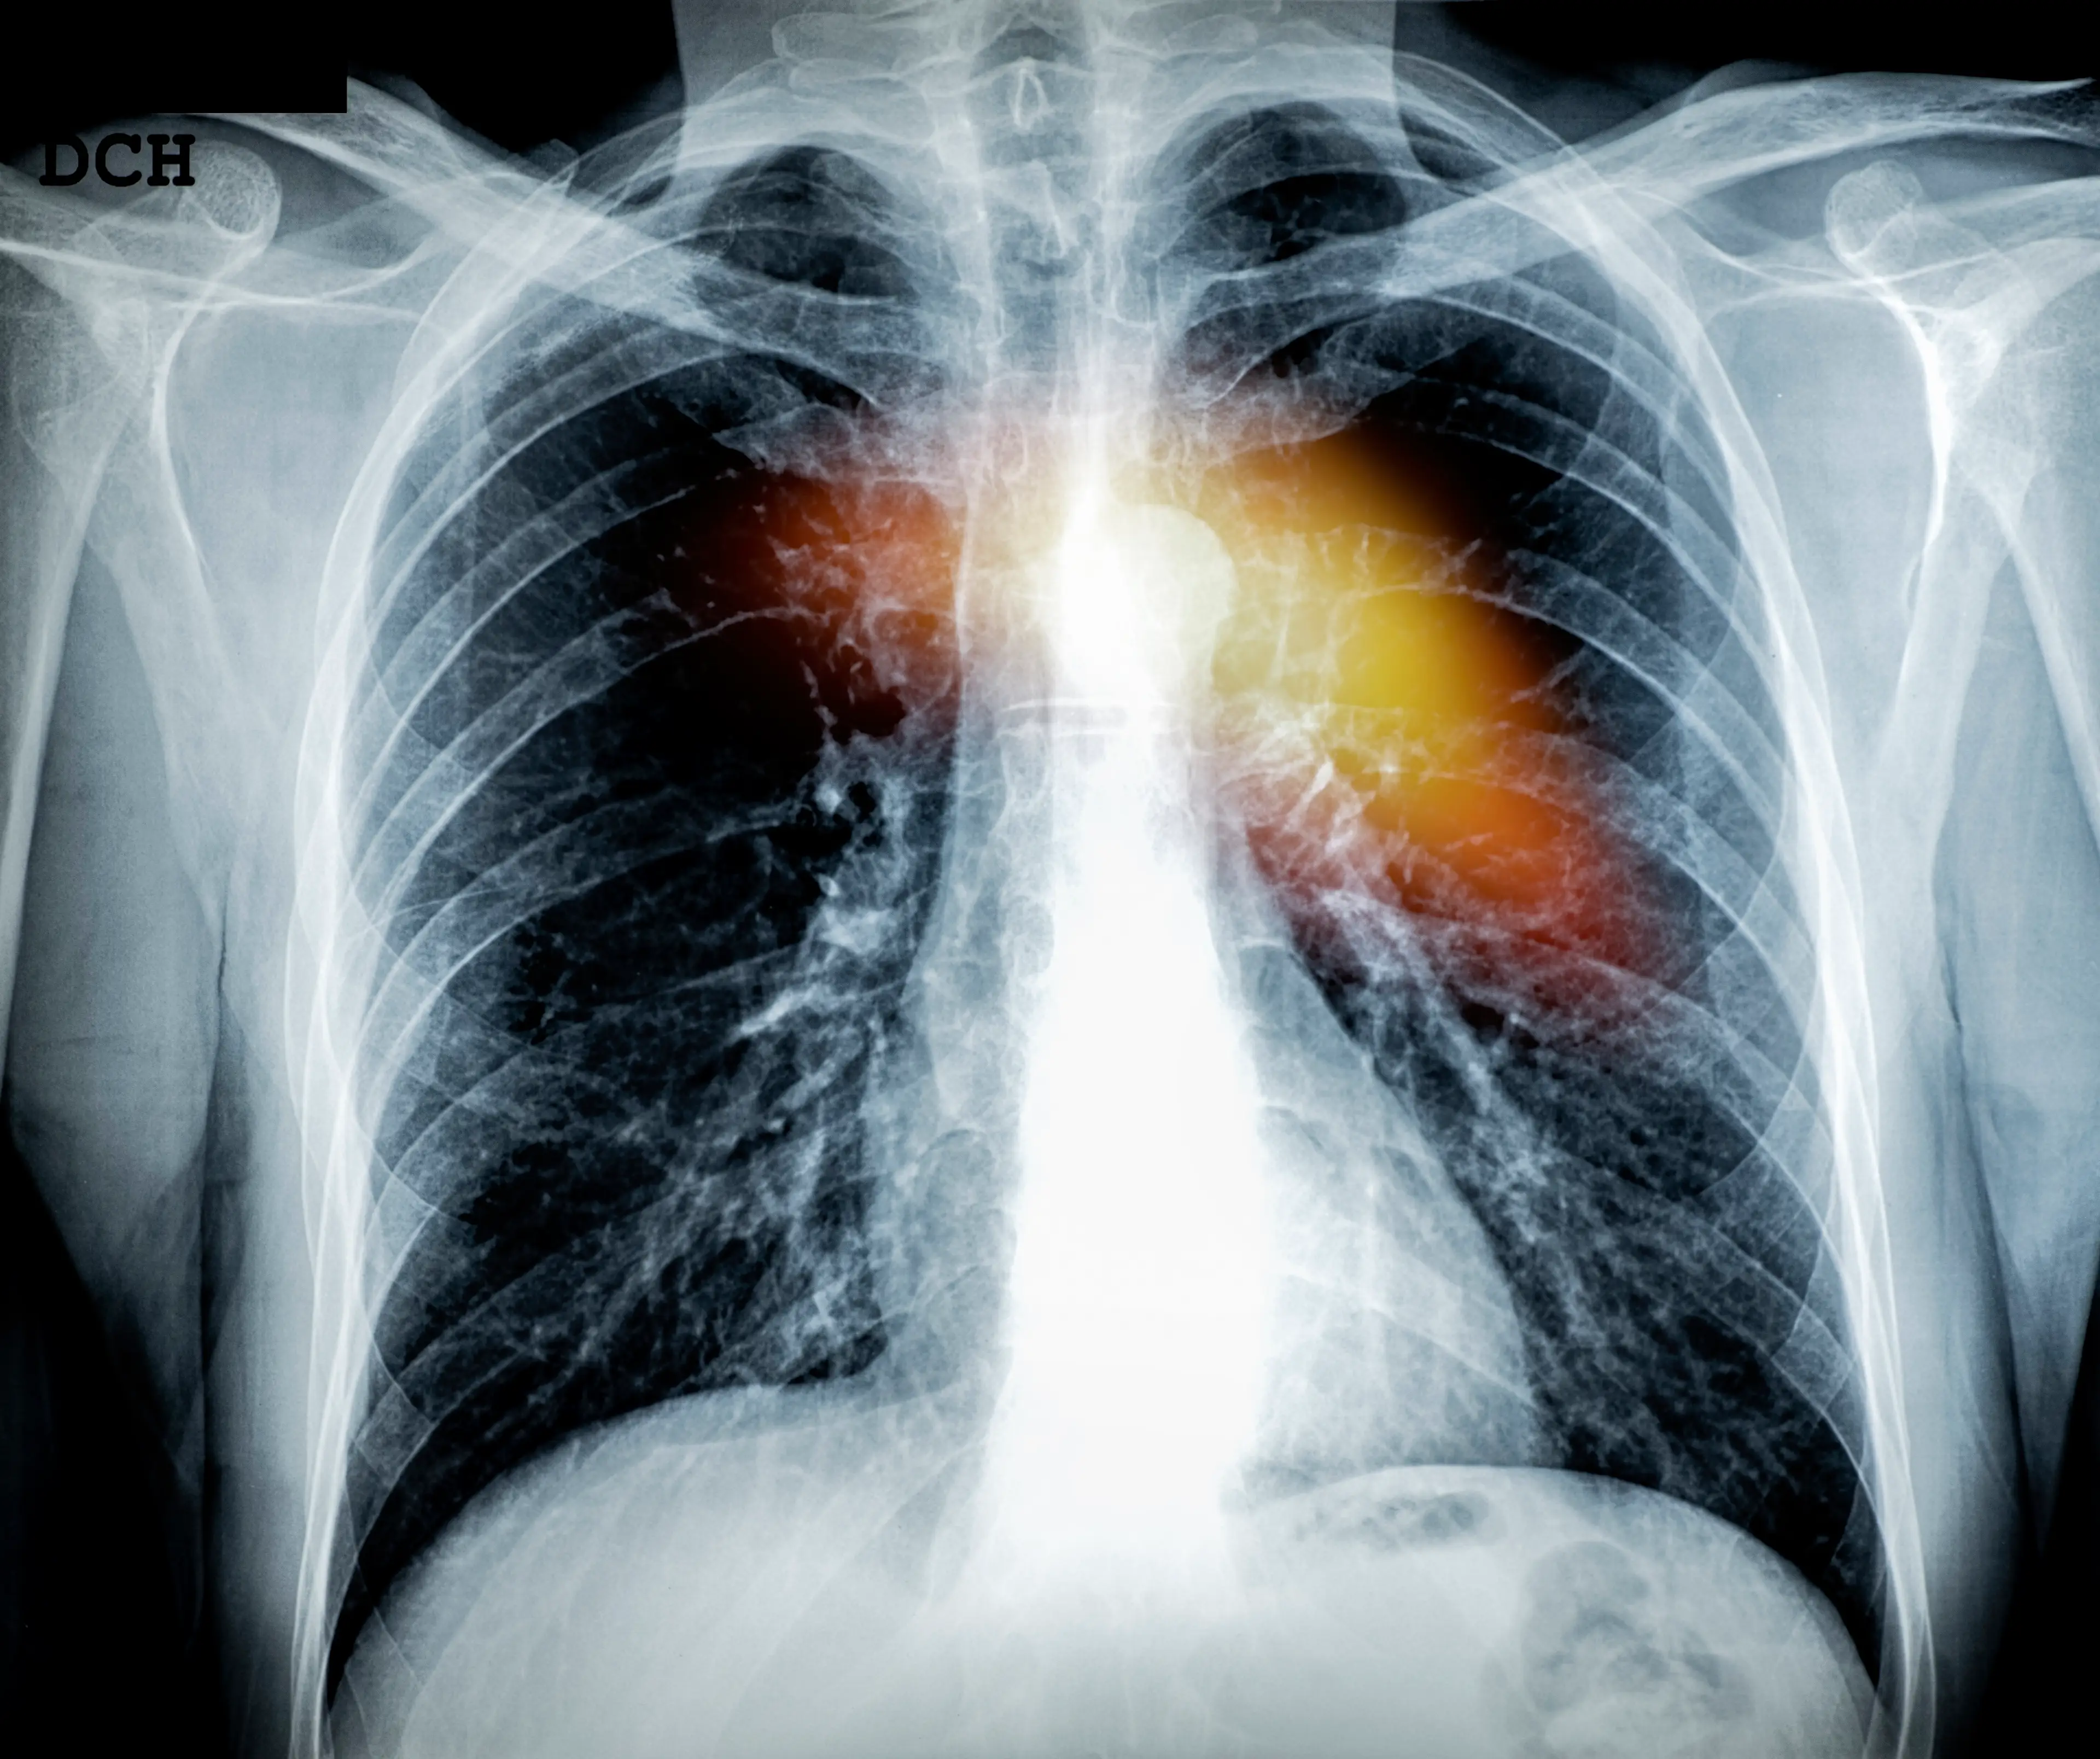

As well as pain when lying down, it can cause debilitating fatigue and extreme breathlessness because of fluid build up in the lungs.

Dr Godeseth explained to The Sun: "Sometimes people [with heart failure] will experience fluid buildup in the lungs which can make it hard to breathe when lying down.